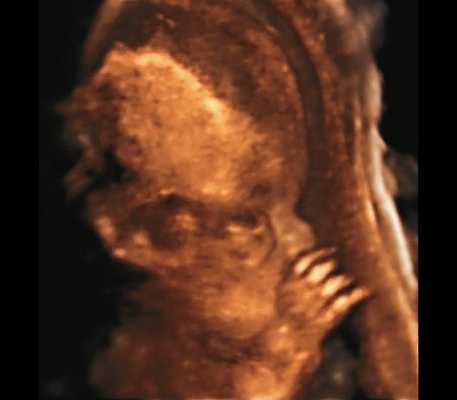

а) Ультразвуковая трехмерная реконструкция (СМ - средний мозг, О - орбита, Ч - червь, М - мозжечок). На плане А показан нижнеаксиальный срез на уровне среднего мозга и орбит, показывающий аномальную бороздчатость медиальной поверхности височных долей (стрелки). Уровень получения этого среза отражен пунктирной линией на плане С. На плане B показан коронарный мозжечковый срез, на котором также отражены выпуклые извилины медиальной поверхности височных долей (стрелки). Пунктирная линия на плане А показывает уровень получения коронарного среза.

а) Уплощенный затылок и выпуклые темпоральные бугры.

б) Представлен косой нижнеаксиальный 2D-срез. Пунктирная линия очерчивает выпуклые извилины с медиальной стороны височных долей (СМ - средний мозг).

б) Нижнеаксиальный ультразвуковой 2D-срез. Уровень среза проходит через средний мозг и орбиты. Стрелки показывают аномально выпуклые извилины медиальной поверхности височных долей (О - орбита)

а) Форма головы "трилистник".

б) Объемная реконструкция. Видны высокий выпуклый лоб, расширенный передний родничок и сагиттальный шов, правильная установка пальцев.

В наблюдениях 1-3 наличие изогнутой бедренной кости (по типу "телефонной трубки") (рис. 1в, 2г, 3г) позволяло предположить наличие ТД I типа. Целе направ ленное исследование головного мозга этих плодов в дополнение к описанным скелетным признакам показало и картину ДВД. Была выявлена аномально повышенная бороздчатость и выпуклость извилин нижнемедиальной поверхности височных долей у плодов в наблюдениях 1-3 (рис. 1а, 2б, 3б). Это позволило установить диагноз ТД I типа.